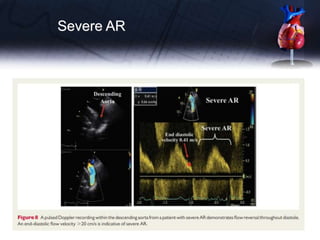

Severe AR

SEVERITY OF AR

Imaging of theflow convergence zone is obtained from the apical three or five-chamber or parasternal long-axis or upper right parasternal views. The radius of the PISA is measured at diastole using the first aliasing. R Vol and EROA are obtained using the standard formulas.